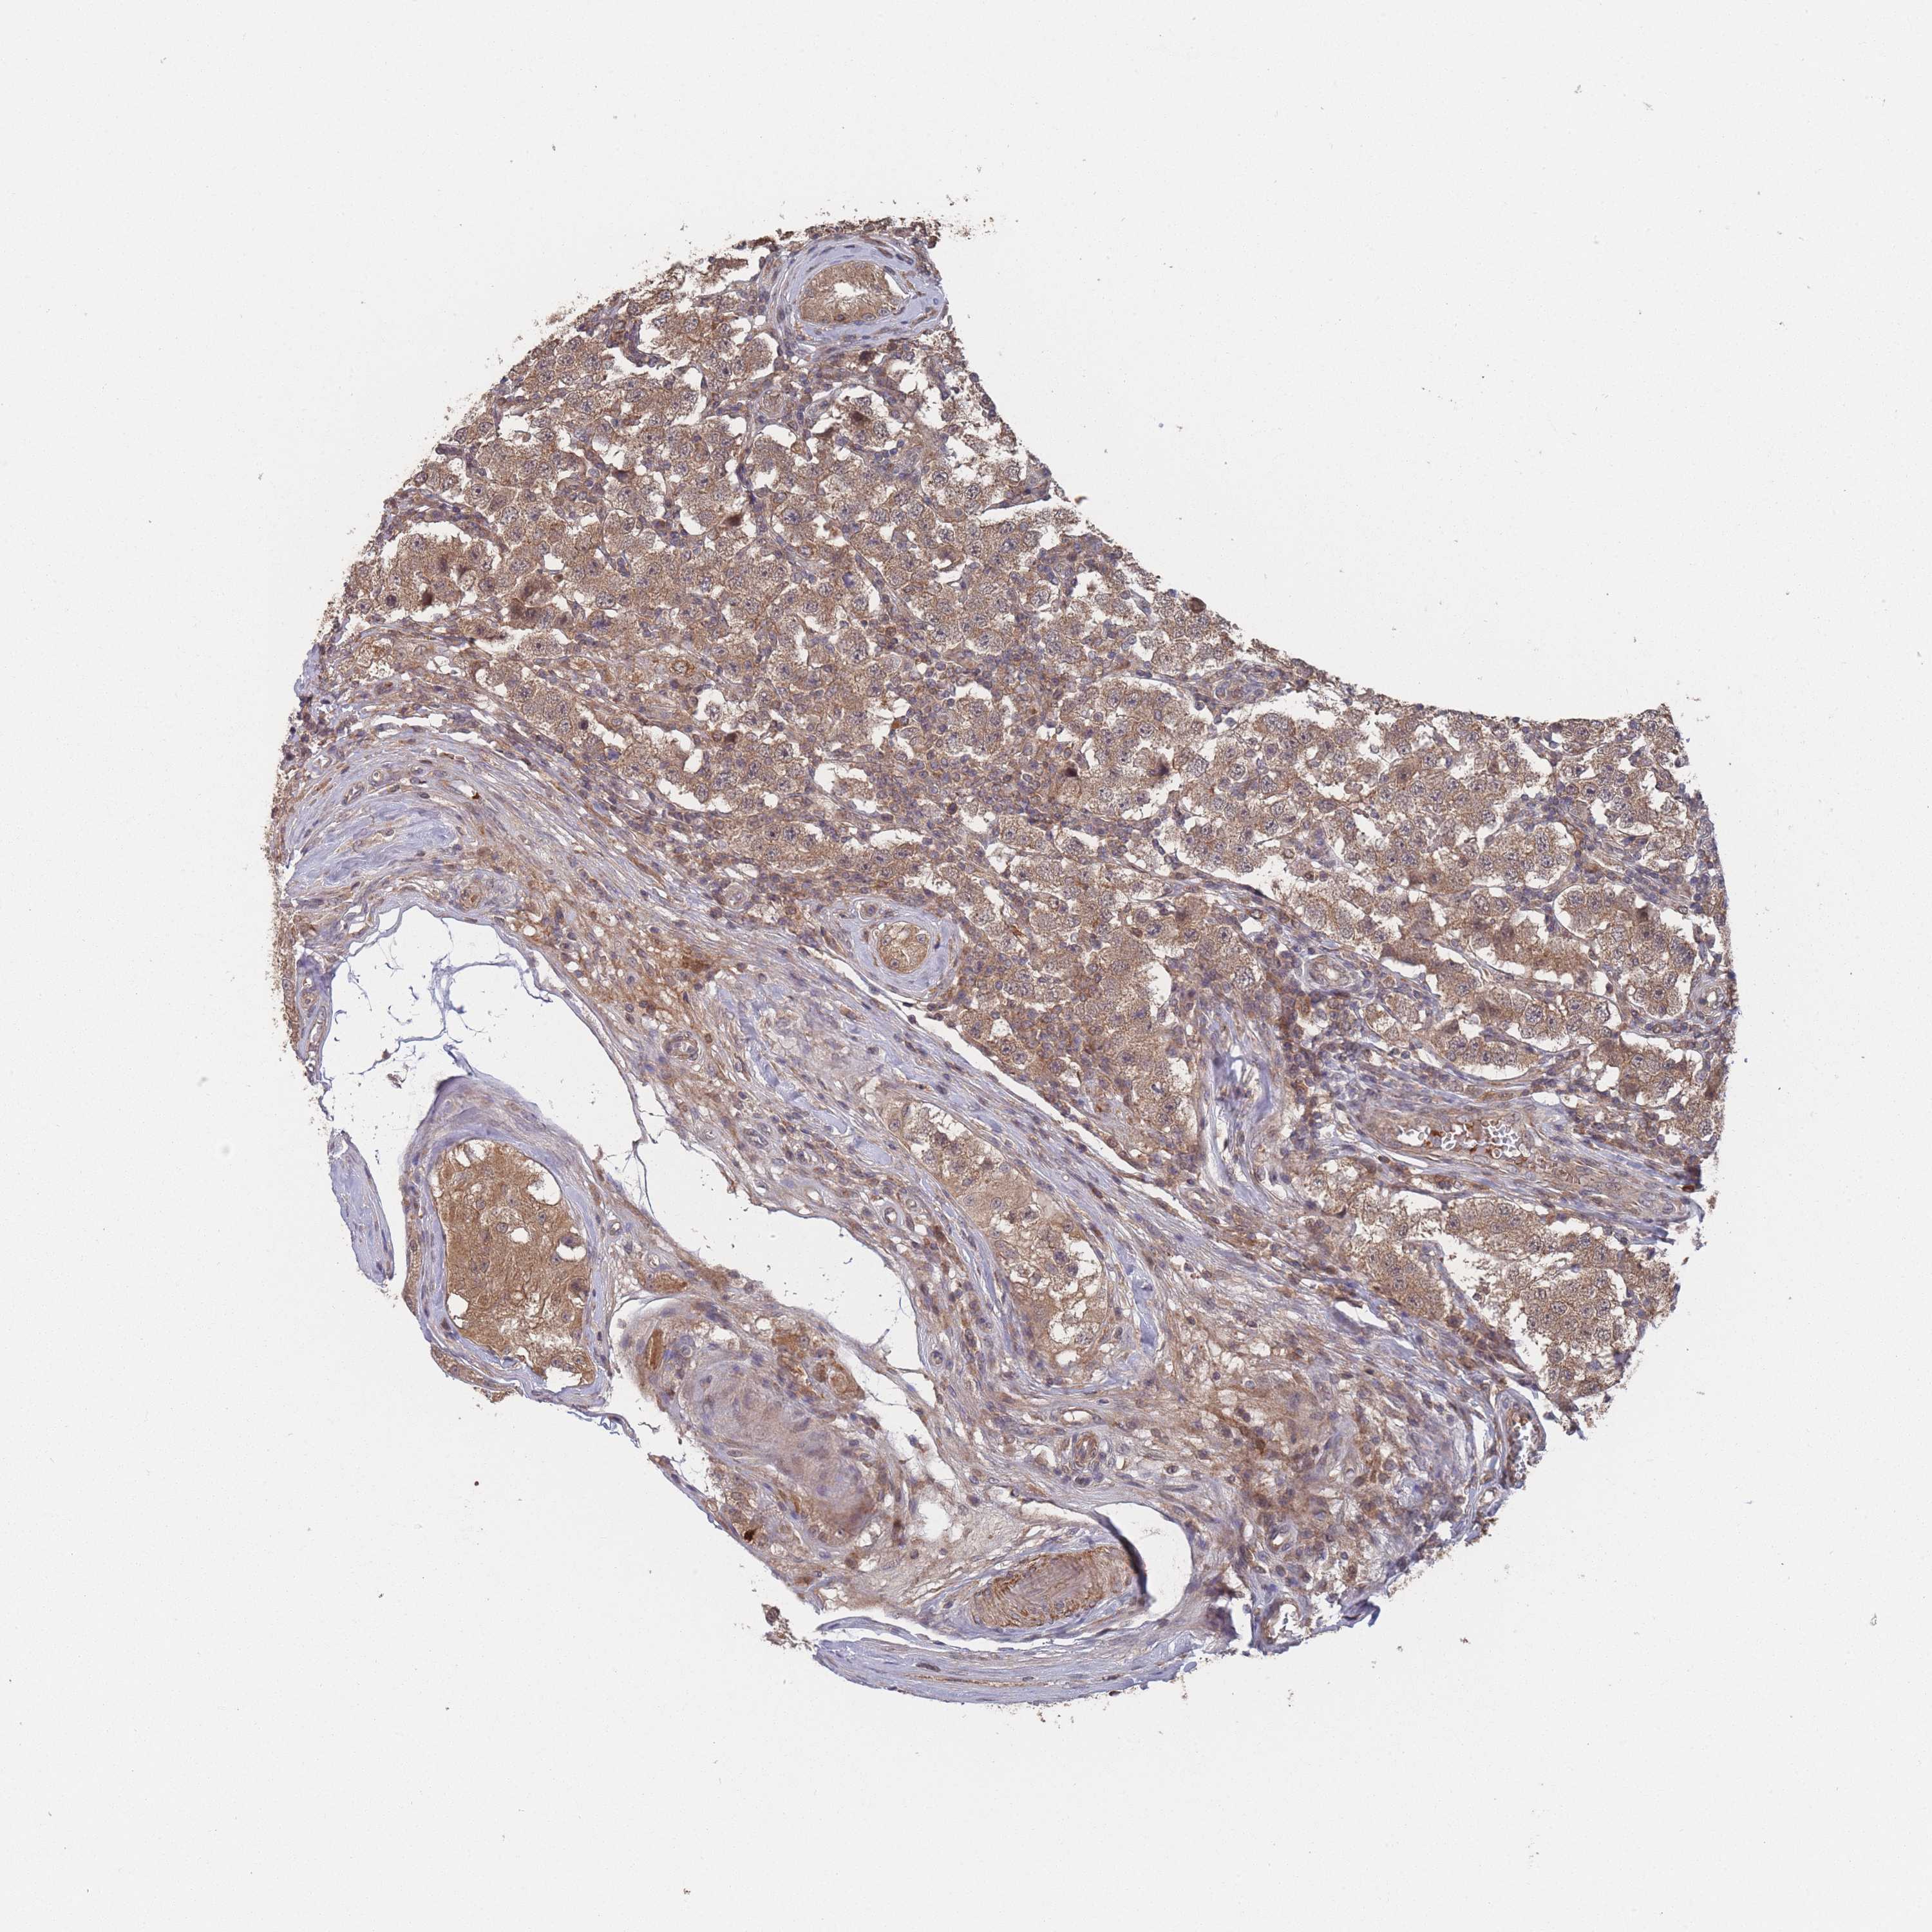

TESTIS CANCER - Protein expressioni

A mouse-over function shows sample information and annotation data. Click on an image to view it in a full screen mode. Samples can be filtered based on level of antibody staining by selecting one or several of the following categories: high, medium, low and not detected. The assay and annotation is described here.

Note that samples used for immunohistochemistry by the Human Protein Atlas do not correspond to samples in the TCGA dataset.

Antibody stainingi

Antibody staining in the annotated cell types in the current human tissue is reported as not detected, low, medium, or high, based on conventional immunohistochemistry profiling in selected tissues. This score is based on the combination of the staining intensity and fraction of stained cells.

Each image is clickable and will lead to virtual microscopy that enables deeper exploration of all samples and also displays staining intensity scores, fraction scores and subcellular localization as well as patient and tissue information for each sample.

Antibody HPA050275

Staining

High

Medium

Low

Not detected

Intensity

Strong

Moderate

Weak

Negative

Quantity

>75%

75%-25%

<25%

None

Location

Nuclear

Cytoplasmic/membranous

Cytoplasmic/membranous,nuclear

Carcinoma, Embryonal, NOS

Seminoma, NOS